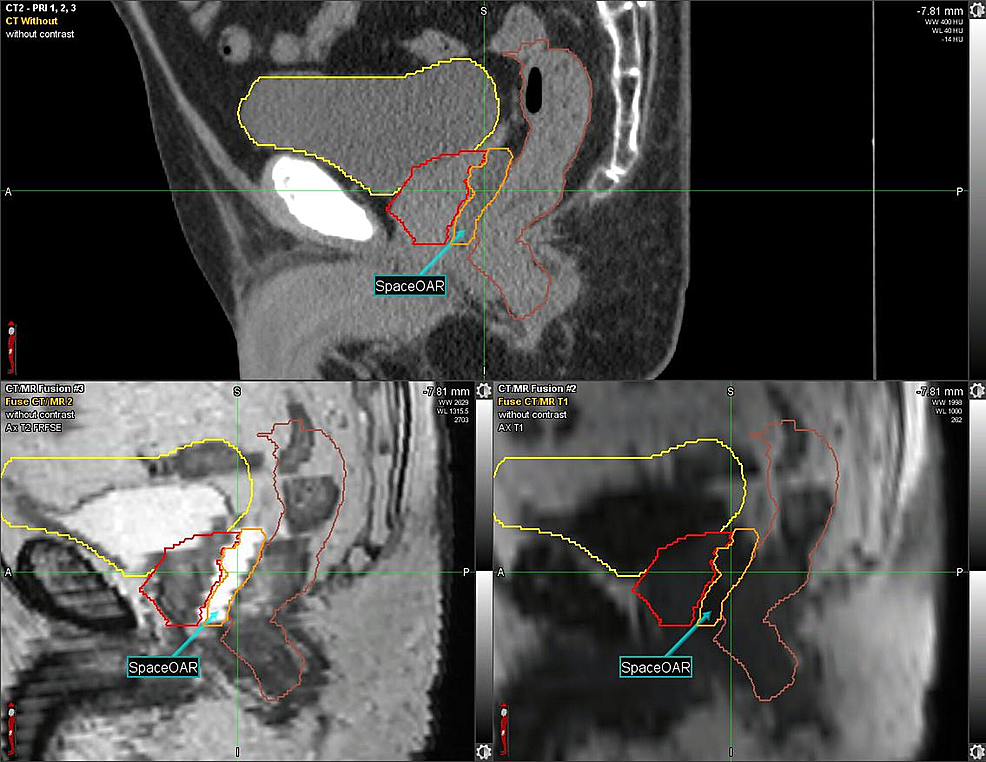

Given the patient’s history of CD, one week prior to RT, the SpaceOAR System (Augmenix; Waltham, MA) was utilized. SpaceOAR is a polyethylene glycol hydrogel that is injected into the perirectal fat and solidifies into an absorbable spacer that separates the prostate and the anterior rectal wall. Prior to spacer insertion, fiducials were placed. The hydrogel was then injected via transrectal ultrasound (TRUS) guidance with no perioperative complications and yielded a roughly 1.14 - 1.21 cm space between the anterior rectal wall and the prostate (Figure 1, Figure 2).